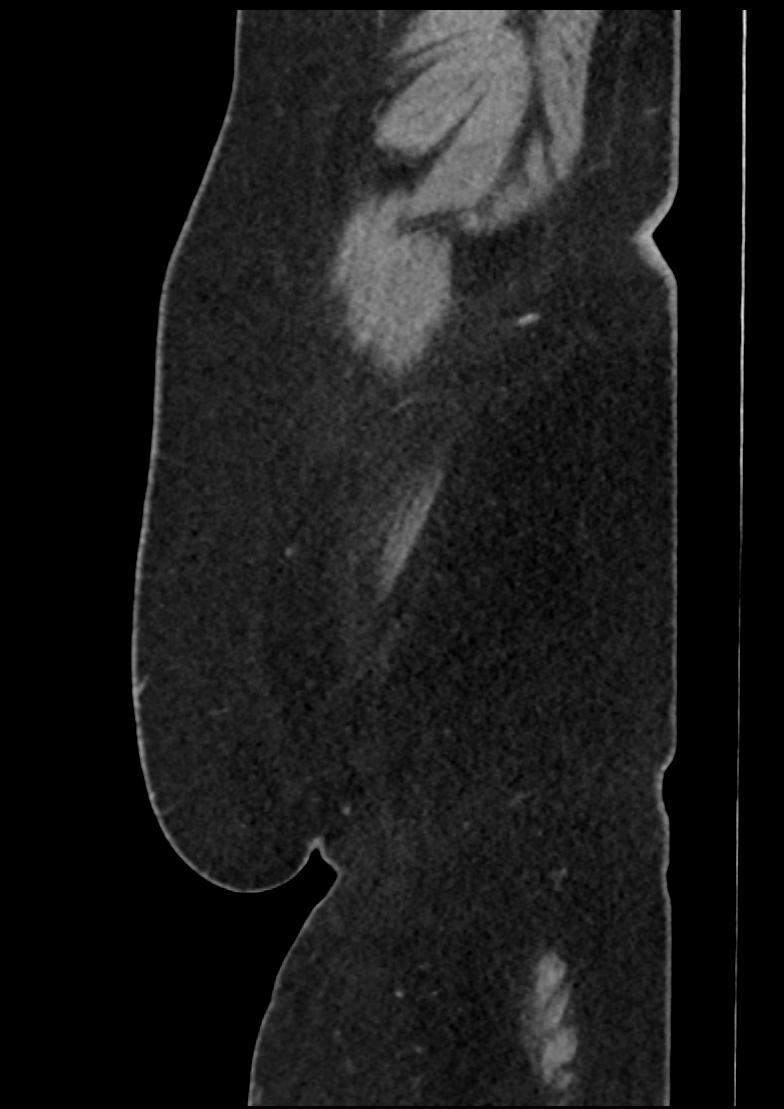

Patient: Padmakumar A. , *1988-04-24, PID: 3000069741773230809

Study Description: CT ABDOMEN

Image Series: Abdomen Sag 3mm [4]